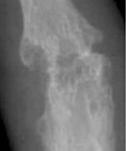

RA – Damaged fingers and wrist RA – Fused wrist bones

https://commons.wikimedia.org/wiki/File:Rheumatoid_arthritis_with_unaffected_carpal_bones_2009.jpg

| Description | English: X-ray of the wrist of a then 58 year old

woman with rheumatoid

arthritis, showing unaffected carpal bones. 8 years later,

she had developed ankylosing fusion of the bones - see File:Rheumatoid arthritis with carpal ankylosis

2017.jpg. |

| Date | 19 January 2009 |

https://commons.wikimedia.org/wiki/File:Rheumatoid_arthritis_with_carpal_ankylosis_2017.jpg

Description    English:

X-ray of the wrist of a 66 year old

woman with rheumatoid arthritis, showing ankylosing fusion of the carpal bones. Previous X-ray showed unaffected carpal bones - see File:Rheumatoid arthritis with unaffected carpal bones 2009.jpg.

Date               19 January 2017